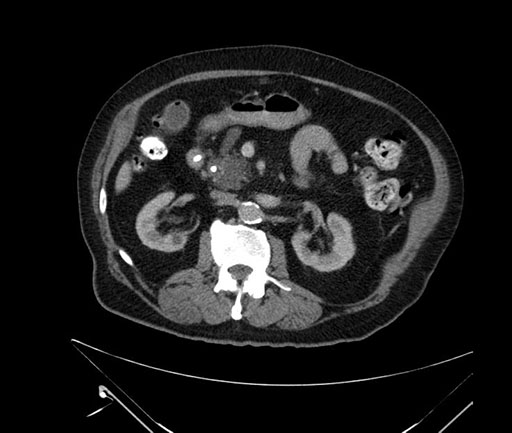

Axial - 3 months prior